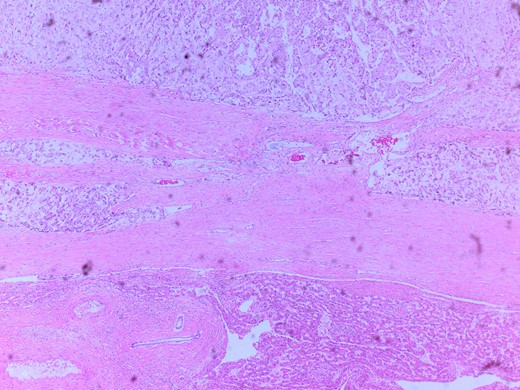

She had a CT chest to complete the staging workup, which was negative for metastasis. Eventually, she had a pancreaticoduodenectomy (Whipple procedure) with smooth postoperative recovery. The patient was discharged home on postoperative Day 7. The final histopathology came as moderately differentiated adenocarcinoma, pancreaticobiliary type with focal squamous differentiation (5%), invasion into the muscularis propria of the duodenum, and positive lymphovascular invasion with 1/12 LN positive for tumor deposits (Figs 3–6). All surgical margins were tumor-free. After a multidisciplinary meeting, the decision was made with proceed for adjuvant chemotherapy. Currently, she is on adjuvant chemotherapy, which she is tolerating well. Follow-up CT CAP at 3- and 6-month intervals postoperatively showed no evidence of recurrence or distant metastasis.

Microscopic image with H&E staining shows a tumor interface with normal liver parenchyma.